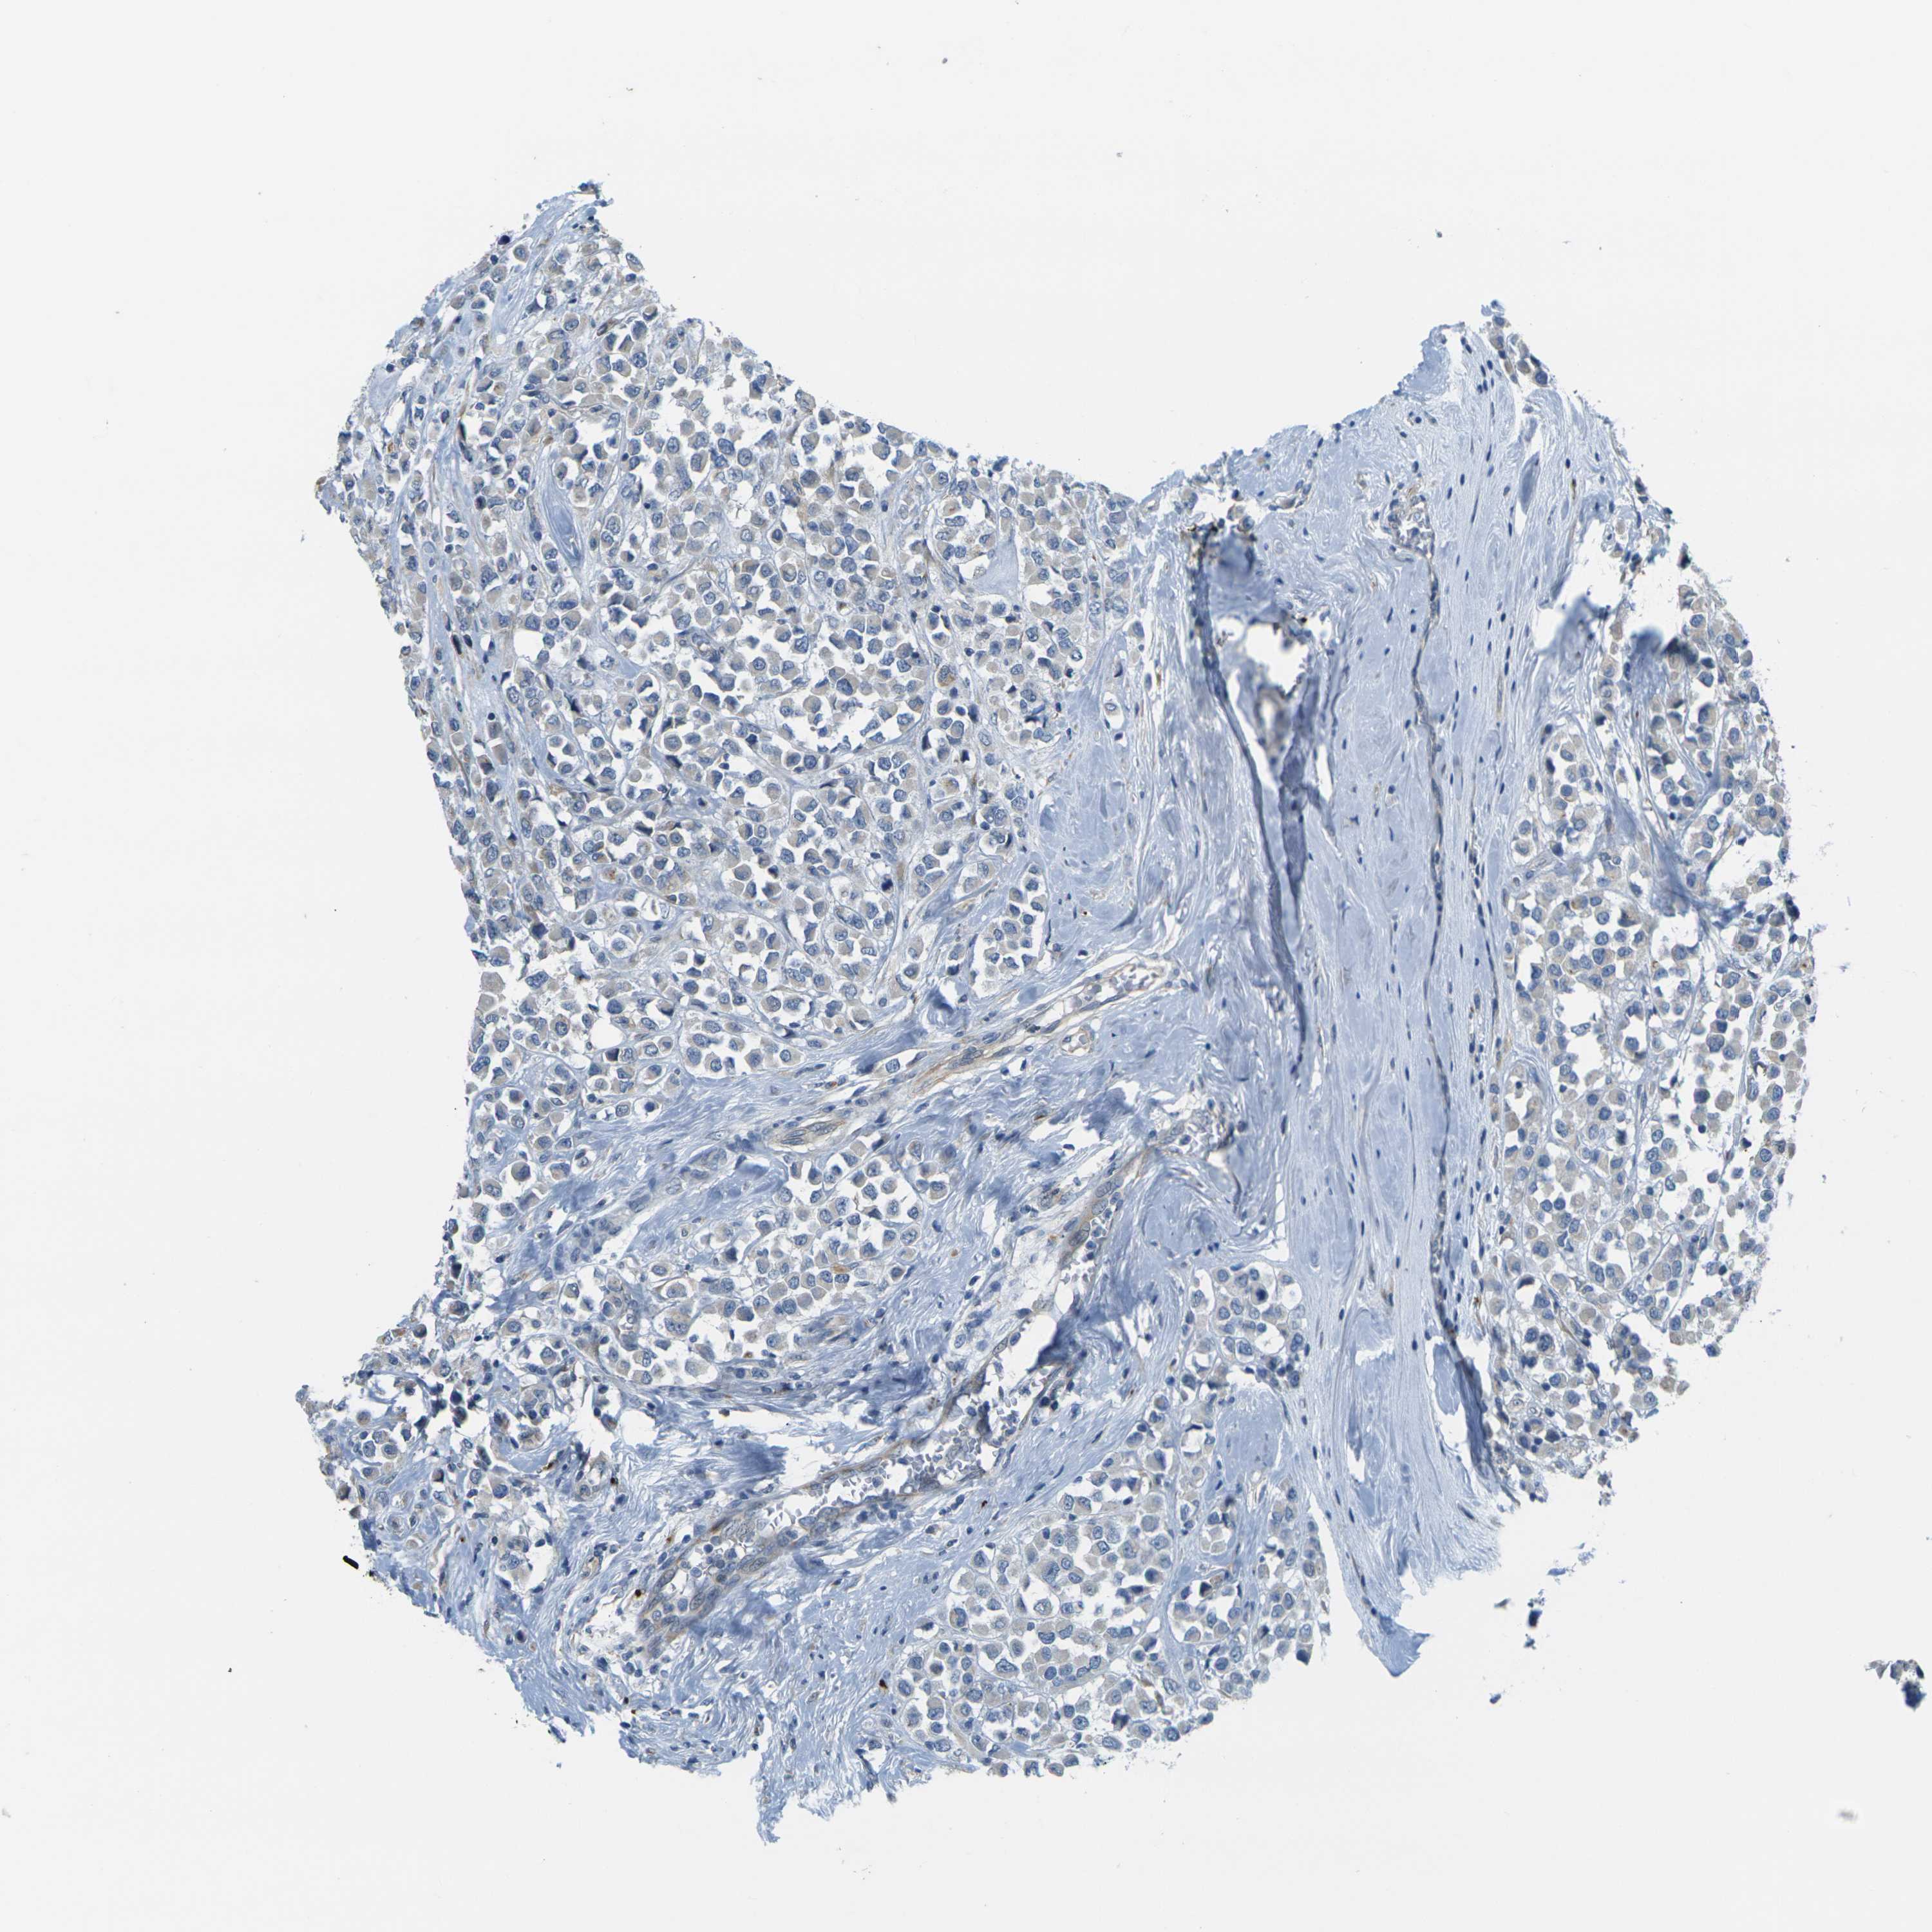

CANCER BREAST CANCER Show tissue menu

BRCA TCGA BRCA VALIDATION PROTEIN EXPRESSION

ANTIBODIES

AND

VALIDATION